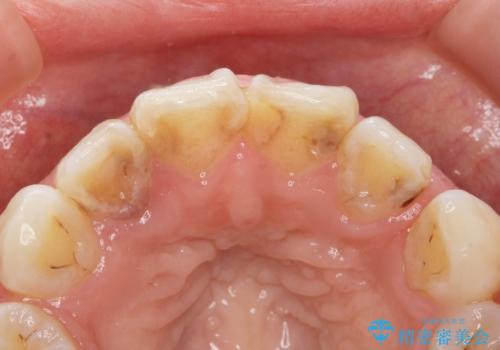

- 上の前歯の色と隙間を気にされ、来院された患者様です。

精査したところ、右上の側切歯(右上2)は神経が死んで変色しており、左上の側切歯と犬歯の間に2mm程度の隙間を認めました。

学生時代に舌側矯正をされており、通院が大変になり治療を途中でやめてしまったとのことでした。

矯正せずに早く治したいという強いご希望により、セラミッククラウンによる補綴治療(上顎両側2の2本)を行いました。